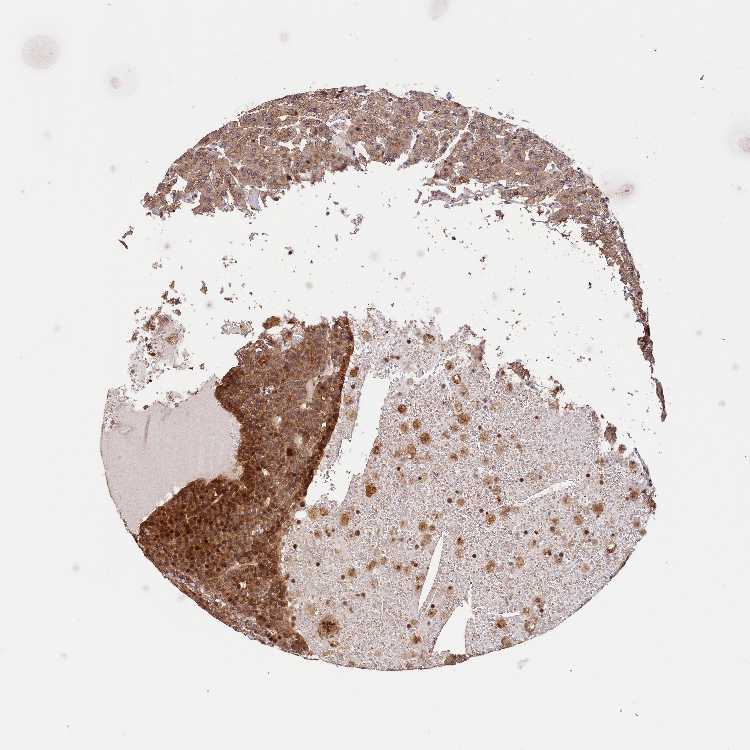

PARATHYROID GLAND - Antibody stainingi

Antibody staining in the annotated cell types in the current human tissue is reported as not detected, low, medium, or high, based on conventional immunohistochemistry profiling in selected tissues. This score is based on the combination of the staining intensity and fraction of stained cells.

Each image is clickable and will lead to virtual microscopy that enables deeper exploration of all samples and also displays staining intensity scores, fraction scores and subcellular localization as well as patient and tissue information for each sample.

Antibody HPA040741Antibody HPA040941

Glandular cells MediumMedium